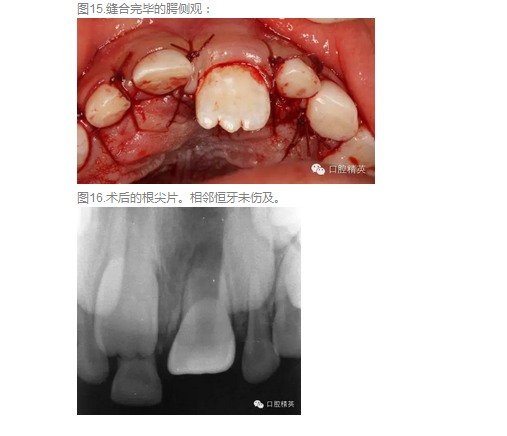

高難度含多生牙囊腫的摘除